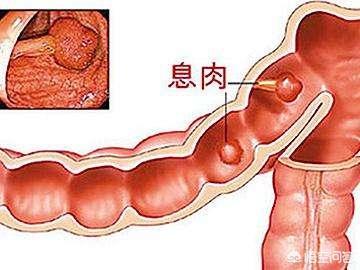

6.腸ポリープ

腸ポリープはがん化する可能性もあり、ポリープが複数ある場合は、早期の大腸がんを避けるため、定期的なフォローアップの大腸内視鏡検査と定期的な生検を受けるよう促す必要があるかもしれない。

腸の腺腫様ポリープ → 腸がん

腸ポリープは、腺腫性ポリープ、炎症性ポリープ、過形成性ポリープに分類される。腺腫性ポリープは5~15年でがんになる可能性がある。炎症性ポリープと過形成性ポリープは、現在のところ癌化する可能性は低いと考えられているが、大腸内視鏡下ではポリープの性状を形態学的に判断することができないため、一般的には大腸内視鏡下で切除し、病理標本にすることが推奨されている。最終的な判定が腺腫性ポリープであったとしても、また嵐の中で "リーキーフィッシュ "を起こさないように、毎年検査を受ける必要がある。

ポリープは間違いなく癌の弟分だが、非常に簡単に癌になる可能性がある。

腸ポリープ

最も有望なミニオンは以下の通り。結腸・直腸ポリープ癌にエスカレートする可能性が最も高く、多くの場合、複数の分布があり、通常は隠れた増殖で、「変形」が結腸癌になることもある。

腸ポリープは表面が非常にもろく、また出血しやすい。 患者は血便に気づいたら受診するが、患者の状態ももはや深刻ではないことが多い。

腸ポリープには大きく分けて炎症性と腺腫性の2種類があり、前者はほとんどが悪性ではなく、後者は悪性の可能性が高い。

統計上、大腸がんの80~95%は腸ポリープから段階的に進行し、その過程には5~10年かかる!

5.腸管ポリープ:家族性多発性腸管ポリープ症は染色体優性疾患であり、一つの遺伝子が多面的に発現する。大腸ポリープは腺腫性ポリープであり、発癌率は50%である。病気の経過の延長、加齢、免疫力の低下により発癌率はさらに高くなり、家族歴があれば男女ともに罹患する可能性がある。家族歴があると男女ともに大腸腺腫性ポリープが発生し、次の世代の年齢が進み、20歳前に大腸腺腫性ポリープがんが発生することさえある。また、一般的な腸管ポリープでも発癌のリスクはあり、腸管腫瘍の大部分は腸管腺腫から緩徐に発生する。 ポリープが大きいほど発癌率は高く、ポリープの数が多いほど発癌率は高く、ポリープの病理学的タイプでは腺腫性絨毛成分が多いほど発癌率は高く、先端部のある腺腫性ポリープは発癌率が低く、基部の広い腺腫性ポリープは発癌率が高く、直腸ポリープは発癌率が高い。